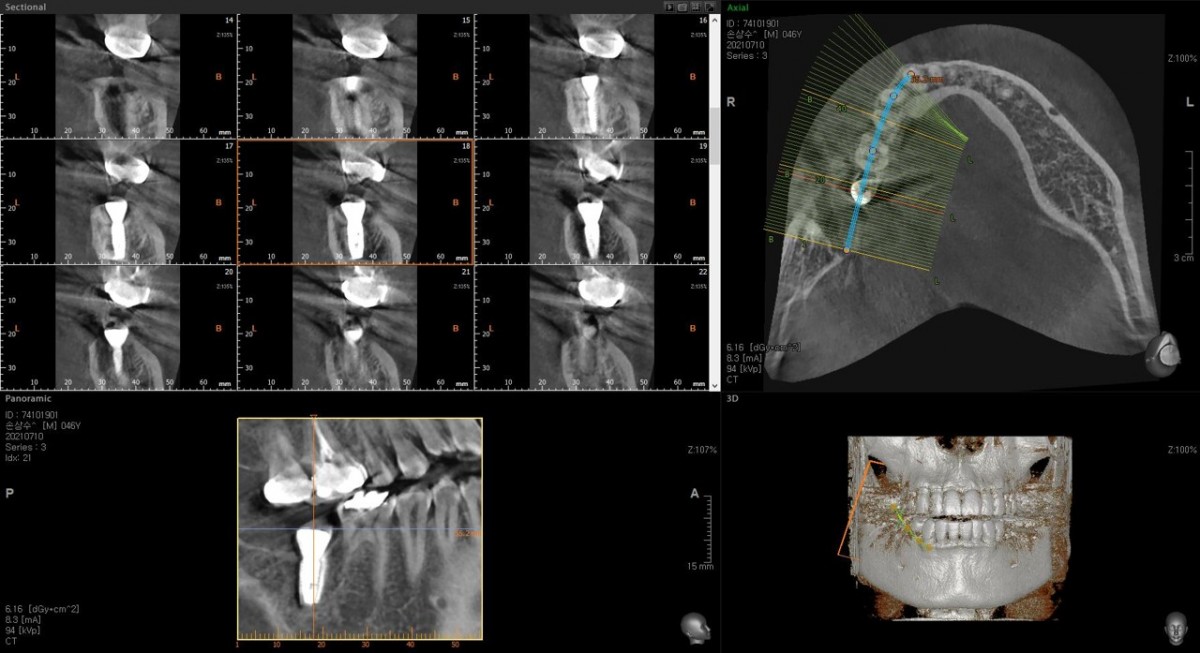

Single implant (staged) Arum NB1, f/u

A 47-year-old male patient had a crown with an ill-fitting margin and crack-tooth syndrome in the lower 2nd molar. No systemic issue.

▲torque value after insertion